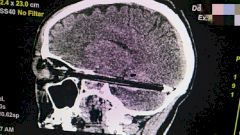

Ручка вошла в мозг через глаз, повредив главное яблоко. При этом инородный предмет занял практически всю полость черепа. Как сообщили врачи «Комсомольской правде в Ростове», ручка прошла в миллиметре от важнейших сосудов и ствола головного мозга, не задев их. Извлекать предмет тоже пришлось с ювелирной точностью. После операции пациенту сделали компьютерную томографию, чтобы исключить возможные риски и осложнения.